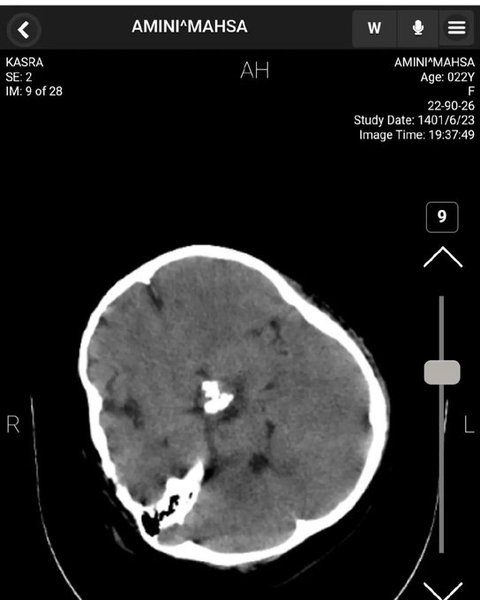

У Twitter якогось Мохаммада, який представився нейрохірургом, опубліковано знімки томографії головного мозку Махси з коментарями.

Згідно з висновком нейрохірурга, на КТ голови Махси не виявлено жодних ознак травми мозку, черепної коробки та кровотечі. На знімках видно сліди зробленої раніше операції.

комп'ютерна томографія, мозок, Аміні

Комп'ютерна томографія мозку Аміні

Знімки КТ підтверджують, що черепно-мозкової травми у Махси Аміні не було

"Ознаки хірургічного втручання є, вони свідчать про лобово-скроневу краніотомію з короткочасною атрофією м'язів та зміни м'яких тканин", — коментує хірург.

Так, за даними нейрохірурга, смерть Махси не могла статися від травм головного мозку.